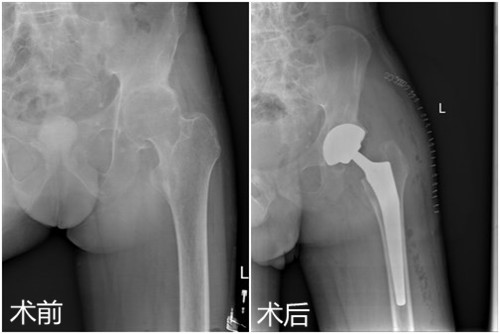

日前,临床医学院/附属医院骨三科为一名35岁强直性脊柱炎累及双侧髋关节男性患者施行了左侧人工全髋关节置换术,术后恢复良好,目前患者已经可以下地行走。该例手术的成功标志着该院骨科在复杂髋关节置换领域的技术日臻完善。

患者田先生,35岁,因身患强直性脊柱炎累及双侧髋关节,行走呈跛行步态,颈部、腰部呈僵直状,只能拄拐行走。两年前,他逐渐出现髋部疼痛不适症状,起初自行在家休息后症状稍有缓解,但两年来上述症状反复出现,并于两个月前明显加重,失去了左侧的行走能力,在当地医院就诊后效果欠佳,慕名来临床医学院/附属医院就诊。临床医学院/附属医院影像学检查显示:左髋股骨头缺血坏死继发关节退变。骨三科朱述浪主任在邀请风湿免疫科专家会诊和多次全科讨论后,决定为患者实施左侧人工全髋置换术,并制定详细的手术方案。手术过程顺利,术后切口愈合良好,术后医护人员对其进行了专业的康复锻炼,患者出院时双侧髋关节屈曲活动度超过80度。患者对临床医学院/附属医院的医疗技术及优质的护理服务予以高度赞扬。